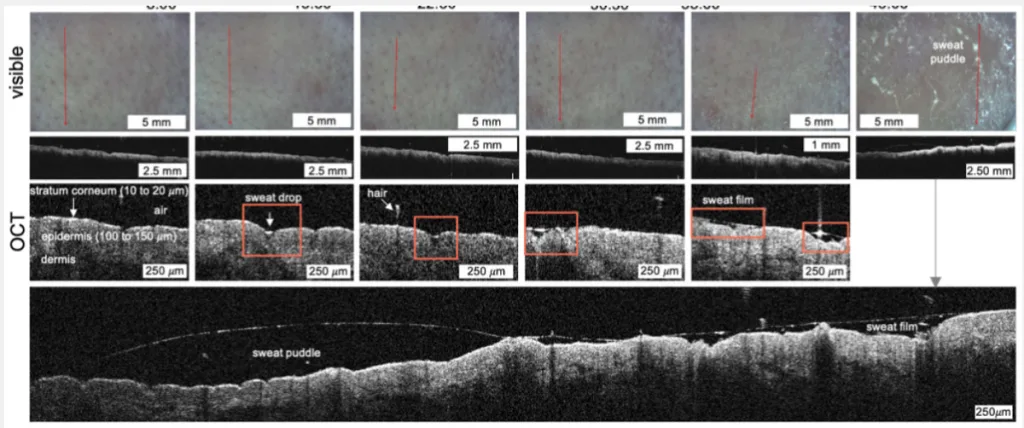

Expresia „picătură de transpirație” este mai mult o metaforă poetică decât o realitate științifică. Cercetătorii au descoperit că transpirația nu iese din pori sub formă de picături individuale, ca apa dintr-o strecurătoare.

- Porii se umplu treptat cu transpirație;

- Când se umplu complet, lichidul se revarsă;

- Acest exces se combină imediat cu cel de la porii învecinați, formând un film de transpirație (cuvântul film mai are un sens, respectiv de strat subțire dintr-un material lichid, solid sau gazos, întins pe suprafața unui obiect solid sau lichid; peliculă) aproape invizibil și extrem de subțire (sub 0,1 milimetri) pe suprafața pielii.

„Imaginea picăturilor care curg pe geamul unei ferestre apare doar atunci când acest film devine suficient de gros pentru ca gravitația să-l tragă în jos,” explică echipa de cercetare, conform Science Alert.

Pe măsură ce corpul li se încălzea, camerele speciale au surprins exact cum porii se umpleau și se revărsau, unindu-se pentru a forma acel film continuu. A fost pentru prima dată când dinamica transpirației la această scară a fost observată direct.